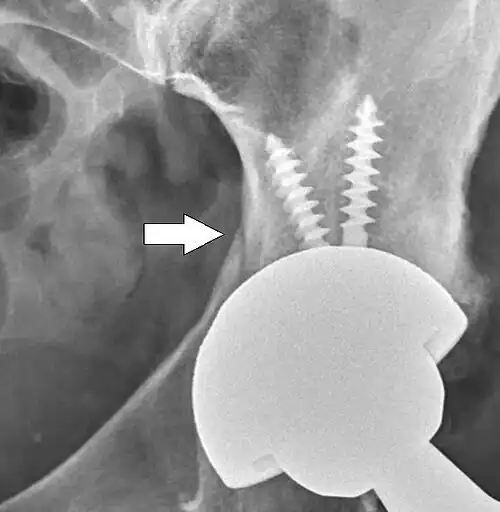

Loosening

On radiography, it is normal to see thin radiolucent areas of less than 2 mm around hip prosthesis components, or between a cement mantle and bone. These may indicate loosening of the prosthesis if they are new or changing, while areas greater than 2 mm may be harmless if they are stable.[45] The most important prognostic factors of cemented cups are absence of radiolucent lines in DeLee and Charnley zone I, as well as adequate cement mantle thickness.[46]